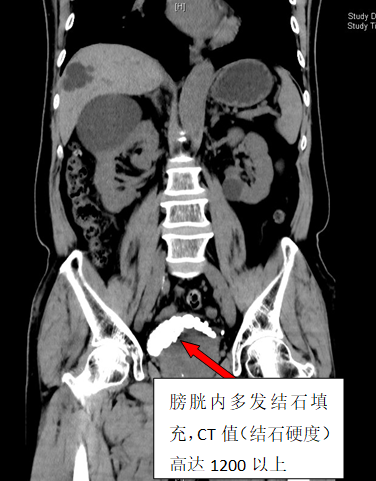

79岁李雄(化名)四年来一直被反复的尿频、血尿、下腹胀痛不适所困扰。在家人多次劝说下,他来到立博体育 泌尿外科二区就诊。CT检查结果显示李大爷膀胱内布满了30余枚结石,犹如月球表面的环形山,其中最大的那颗直径达3厘米,几乎占据了膀胱1/3的空间。

手术当天,泌尿外科二区团队凭借精湛的技术和丰富的经验,为李大爷实施了经尿道钬激光碎石手术。整个碎石过程历时2小时,医护人员精准操作,共发出13800次激光脉冲,将30枚结石打碎取出。术后CT三维重建显示,李大爷的膀胱腔隙内结石已清除干净。